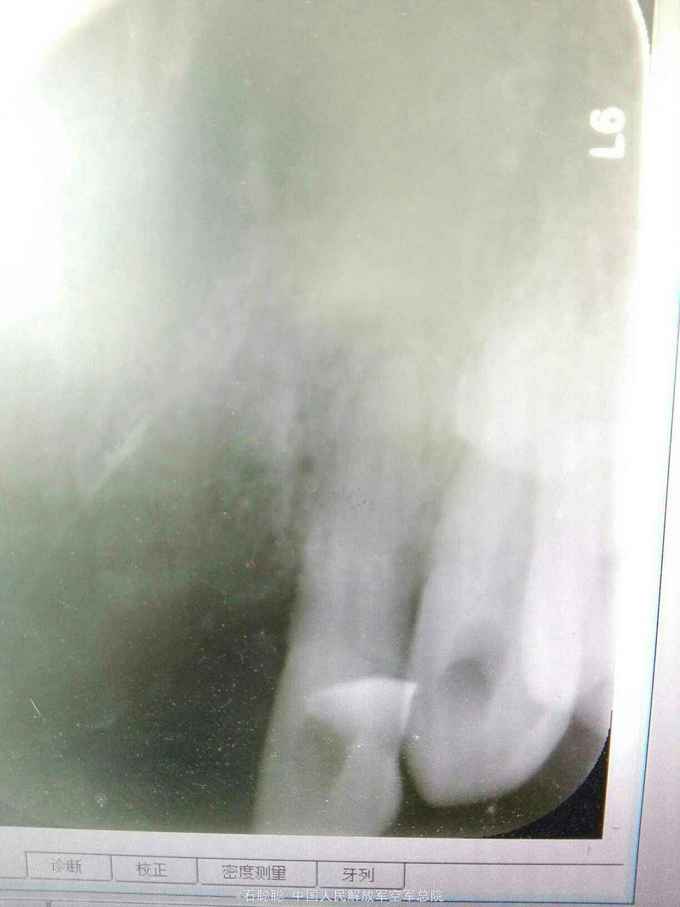

检查:11、21缺失,弹性义齿修复,牙槽脊欠丰满,12、22松动1度,13、23无松动,12、13、22、23未见明显龋坏 根尖片:12、22牙槽骨轻度水平吸收,13、23牙周膜及根尖未见明显异常

诊断:11、21缺失 治疗计划:向患者交代种植、活动、固定义齿修复方案的优缺点,患者考虑到种植周期长、活动修复难以满足美观要求,选择全瓷固定桥修复方案,但患者12、22基牙条件不甚理想,交代患者修复后要严密观察,定期复诊。 处置:12、13、22、23碧蓝局麻下开髓,拔髓,冲洗,置失活剂,氧化锌暂封 一周后复诊:去除暂封,测量根长,12=22=19mm,扩大至25#,13=23=24mm,扩大至35#,大量冲洗,干燥根管,置CP棉球,氧化锌暂封。 一周复诊:12、13、22、23去除暂封,试主尖,冲洗,干燥,冷测压充填,拍摄根尖片,恰填,置干棉球,氧化锌暂封 一周后复诊:12、13、22、23无不适,去除暂封,磷酸锌垫底,树脂充填,预备牙体,排龈,聚醚取模制作临时冠,调磨粘固 一周后复诊:试戴内冠,就位顺利,边缘密合 一周复诊:试戴全瓷桥,由于边缘密合,固位良好,调节正中咬合、前伸咬合、侧方咬合为轻接触,磨光U200粘固